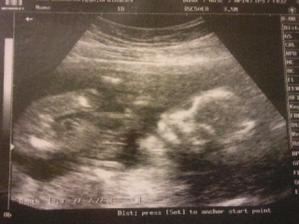

Konečně 26.1. 2010 přišla menstruace a mohla jsem si začít píchat injekce Gonal do břicha (nebolí to) a po 4 dnech kontrolní ultrazvuk, kolik se tvoří vajíček, zatím dobrý na ultrazvuku mý vaječníky začaly připomínat shluk žabých miminek na louži (snad jste to některá z vás někdy viděla, jinak to byla blbá poznámka). Ještě týden injekcí a 10.2. 2010 jsme já i manžel objednaní na osmou ráno opět do Pronatalu, já na odebrání vajíček a manžel na odběr spermatu. V jedenáct jsem šla na řadu, malé množství narkozky a za pět minut jsem to měla za sebou, celkem 6 použitelných vajíček připravené k oplodnění. Každý den jsme si mohli zavolat, jak se naše miminka vyvýjejí a po 5ti dnech byla dvě statečná embrya z šesti připravená na transfer zpět do dělohy. 15.2.2010 byla jedna hodina odpoledne a já pod ultrazvukem sledovala, jak moji drobečci putují zpět do svého domečku, kde se o ně budu 9 měsíců starat. A teď jen čekat, jestli se dostaví menstruace a jinak za dva týdny na krevní testy.

No samozřejmě, že když se po týdnu menstruace nedostavila okamžitě jsem testila už dávnou koupeným těhotenským testem a viděla ty dvě nejkrásnější čárky pod Sluncem. Na krevní testy jsem šla celá natěšená a pyšná na svoje těhotenství. Potvrdilo se, jste těhotná, zazněla ta nejhezčí věta od sestřičky v Pronatalu, teď se jen objednejte na ultrazvuk, tam se dozvíme, kolik jich vlastě budu nosit.